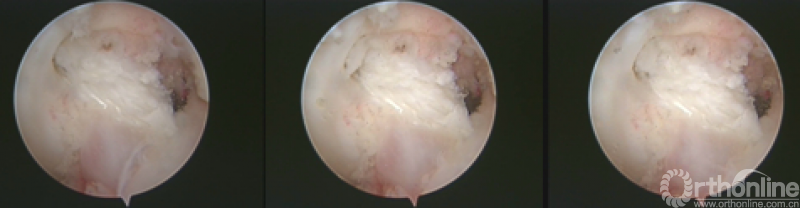

*连续镜下观察移植韧带无明显拉伸

MRI